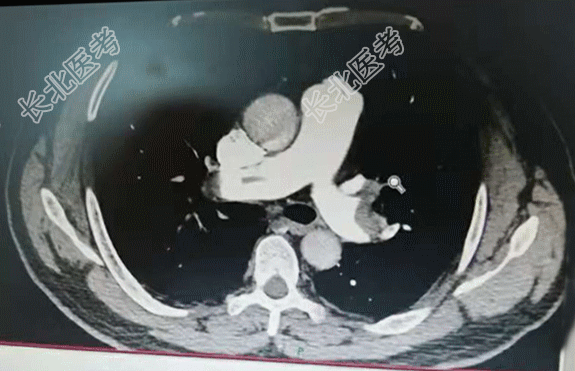

【现病史】2天前,患者无明显诱因出现右侧胸痛不适感,伴呼吸费力。当时无咳嗽、咳痰、发热等症状。以为是劳累导致的症状,经休息后症状缓解不明显,今晨起疼痛症状加重,家属拨打120急救送入我院,急诊科查指脉氧98%,行肺部CTA检查时指脉氧降至92%,肺部CTA显示:肺栓塞。诊断为:肺栓塞。发病以来饮食、睡眠差、小便正常,大便未解,体重无明显变化。

【辅助检查】肺部CTA显示:肺栓塞。心电图:标3、Avf、V₄-V₆导联T波改变。